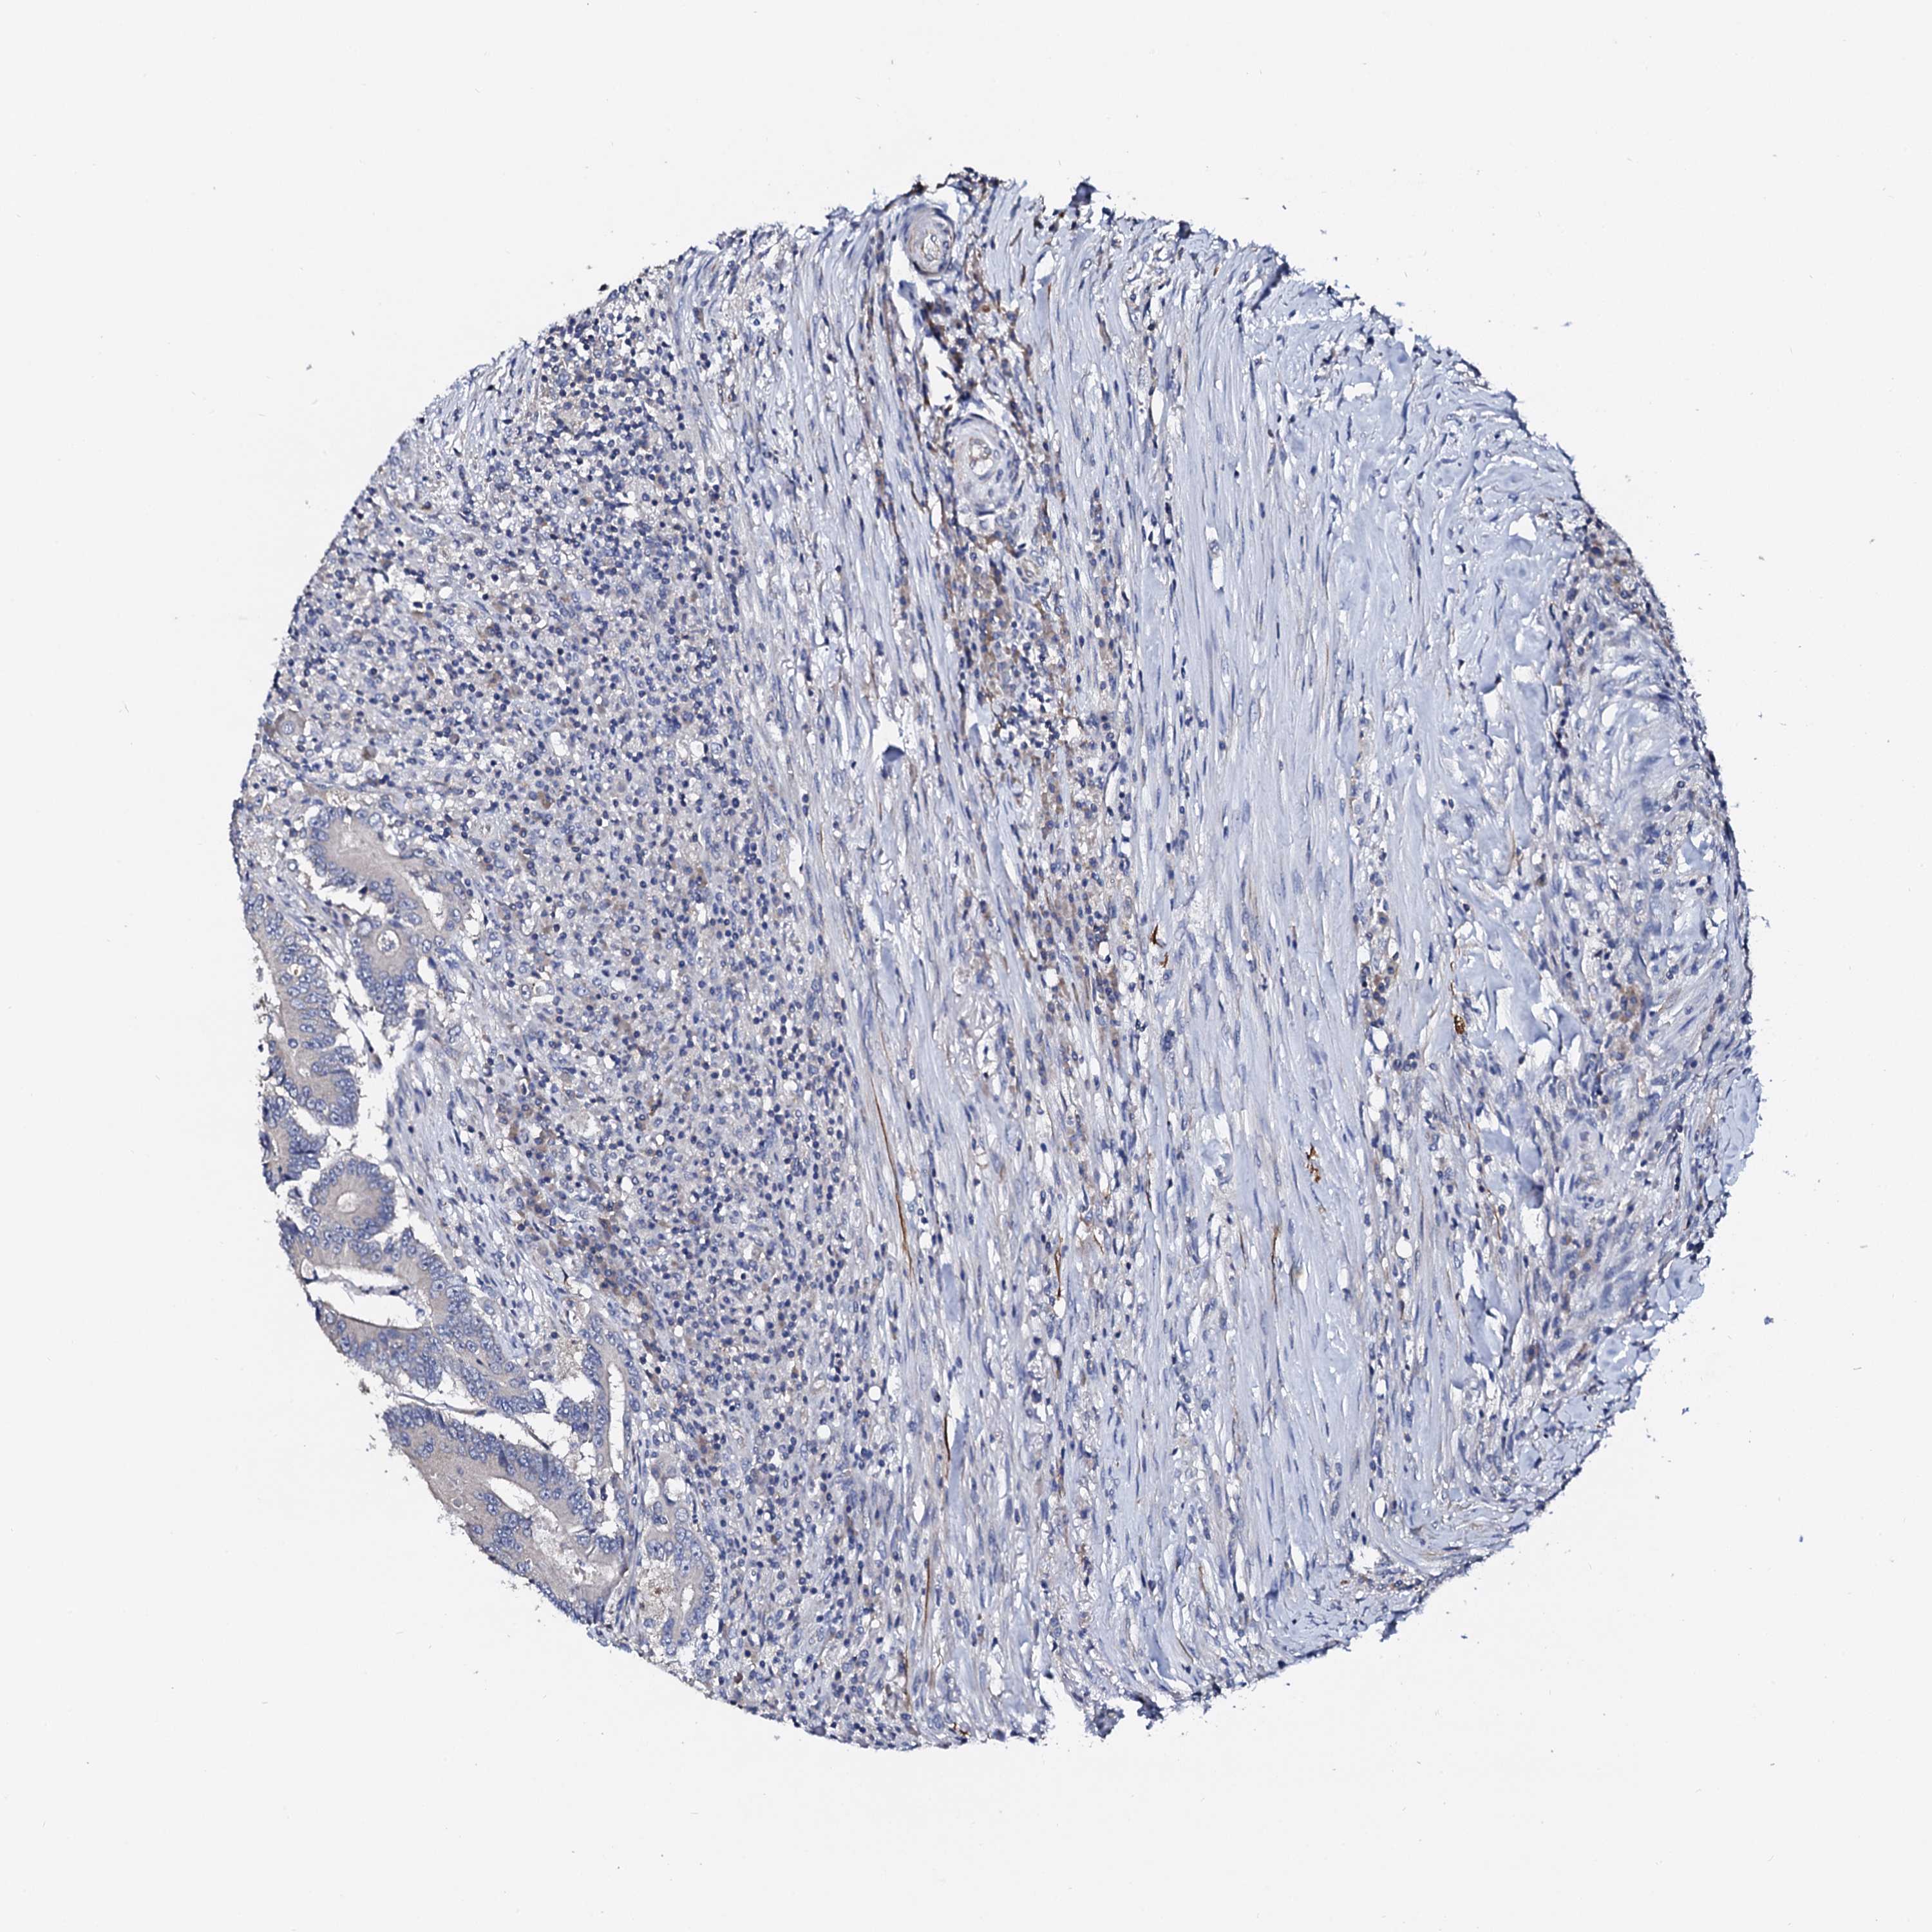

CANCER COLORECTAL CANCER Show tissue menu

Colorectal cancer

Human cancer

Colon adenocarcinoma